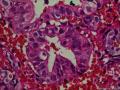

子宫内膜1

性别年龄49临床诊断性质待查?

一般病史月经淋漓不尽2月余

标本名称诊刮内膜

大体所见灰褐膜样组织2*2*1cm一堆。

子宫内膜不典型增生

复杂性增生+异型

细胞聚集,腺体崩解,出血背景, 感觉还是个月经期子宫内膜。